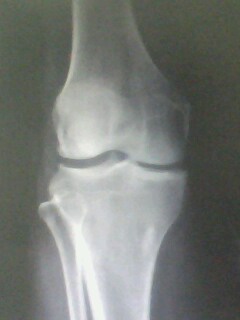

以下是引用muzi888在2010-5-12 11:02:00的发言:[br]骨岛,髁间棘及胫骨关节面有骨增生改变,余无异常。

以下是引用随光逐影在2010-5-12 14:43:00的发言:[br]1)胫骨上段骨岛。2)膝关节退行性改变。